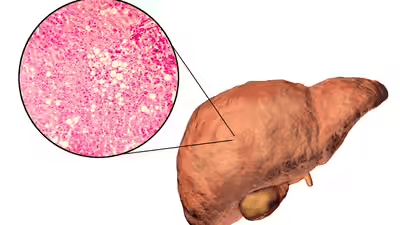

When you eat or drink something high in fructose (the sugar in fruit juice, soda, or processed foods), your liver becomes the main processing center. Unlike glucose, which muscles can use for fuel, fructose must be metabolized entirely by the liver. When there’s too much of it, your liver starts turning that excess into fat. Over time, this fat builds up and leads to non-alcoholic fatty liver disease (NAFLD)—a condition now seen in both adults and teenagers.

Studies suggest that by the time most people are diagnosed, fat already covers more than 5–10% of their liver. At that stage, the organ’s ability to detoxify and balance hormones is compromised. And if left unchecked, it can progress to inflammation, scarring, or even cirrhosis.